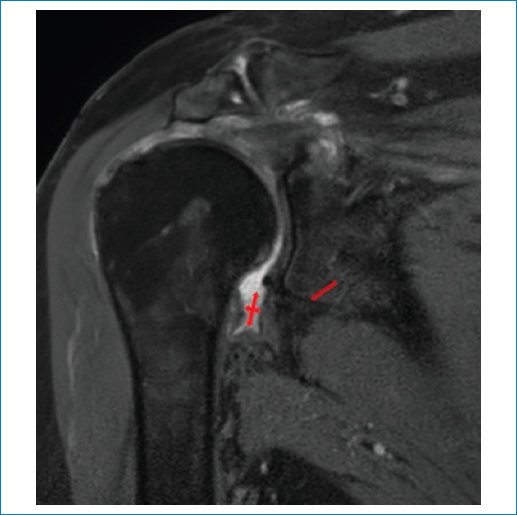

En nuestra serie aplicamos los criterios de Emig et al.11, que incluyen la hiperintensidad o el engrosamiento del ligamento glenohumeral inferior > 3 mm (Figs. 1 a 3), el engrosamiento capsular del receso axilar (con valores que varían según los estudios, pero descrito en general como > 7 mm) (Fig. 3), el engrosamiento del ligamento coracohumeral > 4 mm (Fig. 4), la infiltración grasa y la hiperintensidad del intervalo rotador (Figs. 5 a 7), y la obliteración de la grasa subcoracoidea (descrita como ausente, parcial o completa) (Fig. 8).

Figura 1. RM en secuencia DP-FS, corte coronal. Se observa un engrosamiento del ligamento glenohumeral inferior con señal hiperintensa en el receso axilar (flecha).